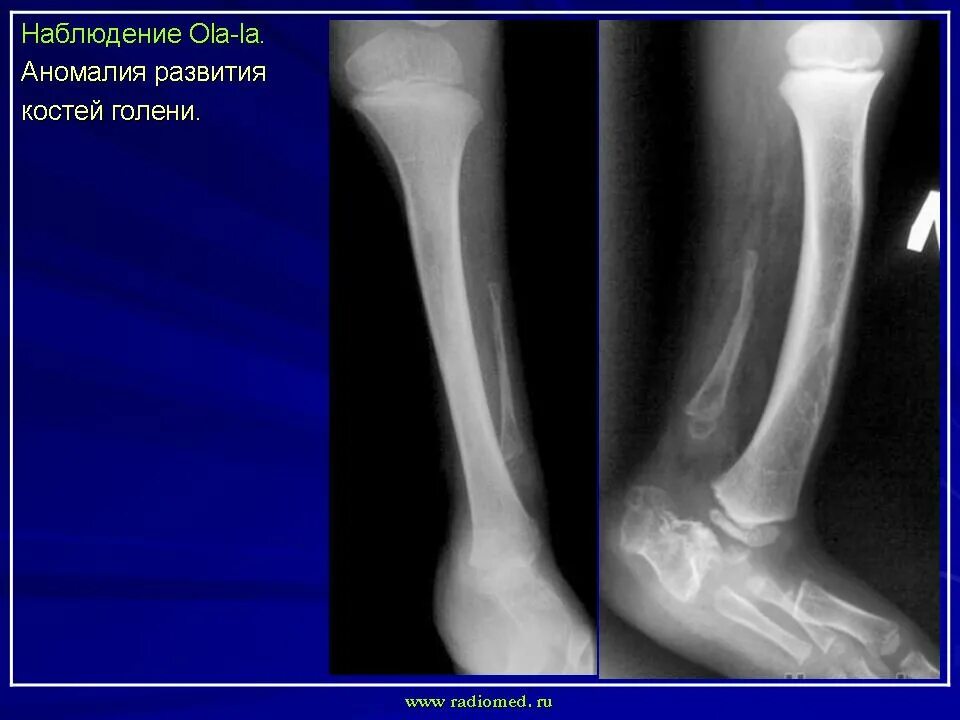

Аномалии костей